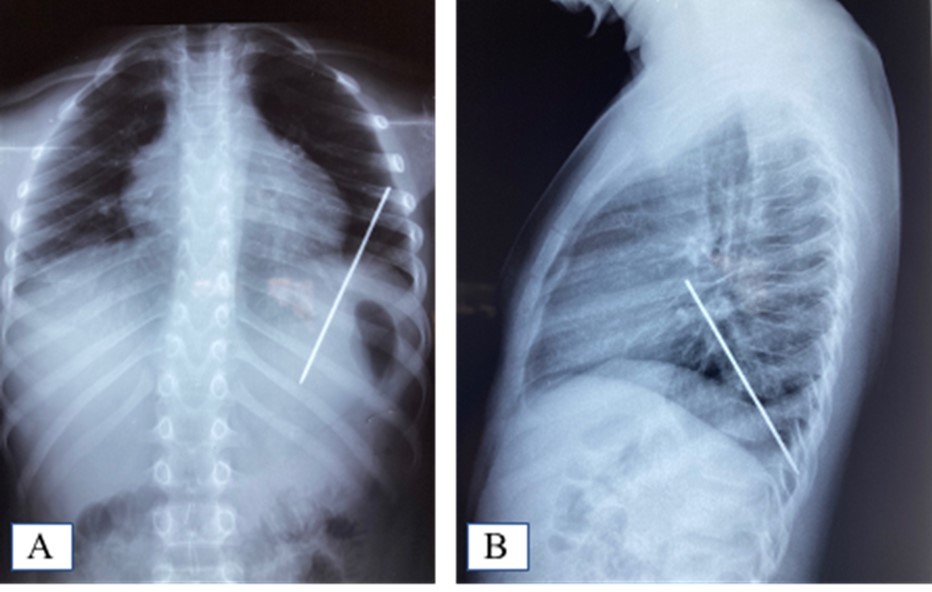

AD, aged 10, with no particular pathological history, was referred to us for the management of a post-traumatic intrapulmonary foreign body. The traumatism would have occurred one month earlier, during a playful accident. He would have received from his brother, at the level of the left hemithorax, a blow with the metal tail of a comb. The latter would then have been torn off by the child but without the tail. This would have caused a minimal wound, associated with an intense chest pain, without dyspnea, or cough, justifying local care and treatment with analgesics. The incident was withheld from parents. On admission, there was a punctiform scar in the 2nd left intercostal space, about 5 cm from the sternal border. The pulmonary fields were free. The rest of the exam was normal. The biological results were normal. A first chest x-ray showed a metal rod, oblique downwards, backwards and inwards, going from the 5th to the 11th left costal arch (Figure 1). The computed tomography scan of the chest showed the metal rod in the lung parenchyma. It was approximately 105 mm long and stayed away from the heart and the great vessels. There was no pulmonary parenchymal abnormality, pleural effusion or obvious bone lesion (Figure 2). Two subsequent X-rays showed its migration downwards, inwards and backwards with an upper pole sitting opposite the posterior arch of the 8th rib. A left posterolateral thoracotomy approach allowed the removal of the metal rod lodged in the lower lobe of the lung (Figure 3). The postoperative period was unremarkable. The ablation of the drains was carried out on the5th postoperative day. The patient was discharged on the 8th day. Reviewed in the6th postoperative month, his examination was normal.

Figure 1.A. Frontal chest X-ray showing the foreign body; B: Foreign body sparing the diaphragm on the lateral chest X-ray